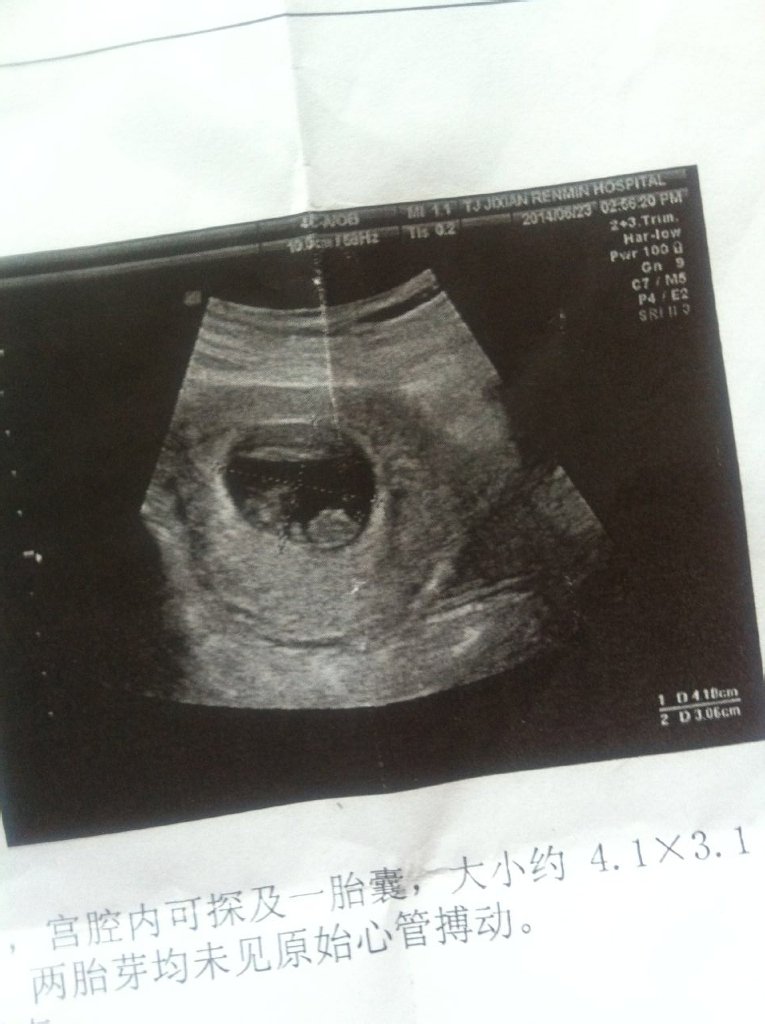

这是怀孕50天的B超 谁能告诉我 什么意思?要做流产吗? 这是怀孕50天的B超。谁能告诉我 什么意思?要做流产吗? 点击展开 戒毒 2014-06-26 14:46 为您推荐: 其他回答 主要是看字 ╭蛊毒〃 2014-06-26 14:48 你好,你的检查是有双胞胎的可能,一般怀孕30—40天形成的是胎囊,40—50天形成的是胎芽,50—60天形成胎心,可以再复查一下。 上白城 2014-06-26 14:47 相关问题 怀孕45天孕酮低 50天去做b超很正常 请问会流产吗? 怀孕50天做仰卧起坐会导致流产吗? 我刚怀孕50天,今天早上发现有棕色分泌物是流产的先兆吗?我应该怎么办?